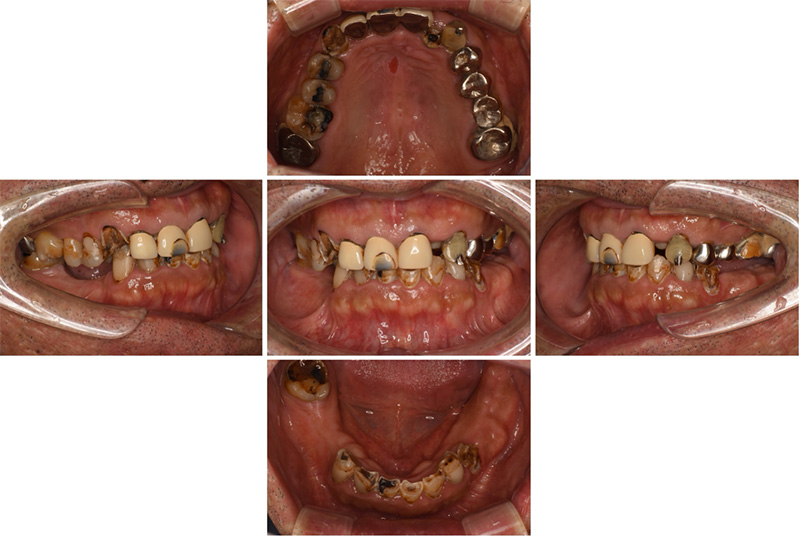

57歳男性

治療前

治療後

| 施術名 | インプラント治療 |

| 施術の説明 | インプラント治療とは、歯を抜いた所にチタン製の人工歯根を埋入し、新しく歯を入れる方法です。 |

| 施術の副作用 (リスク) | 腫れや疼痛を感じる、違和感を感じるなどの症状を生じることがあります。 |

| 施術の価格 | 53万円~+消費税 |